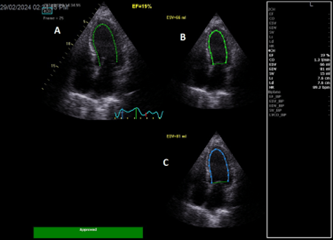

Echocardiography done urgently, while patient was receiving inotropic support, and showed a reduced LVEF at 19% (Figure 3).

Figure 3: A: Apical 4 chambers view showing automatic left ventricular ejection fraction at 19%. B: LV end systolic volume at 66ml. C: LV end diastolic volume at 81ml.

LA=left atrium; LV=left ventricle; RA=right atrium; RV=right ventricle; EF=ejection fraction; ESV = end systolic volume; EDV = end diastolic volume.